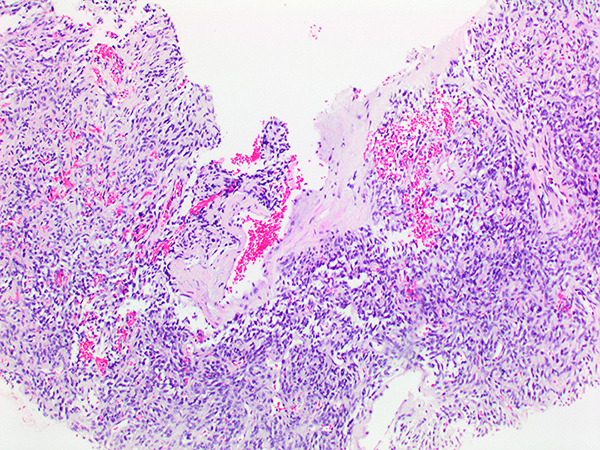

Histologically, these tumors are characterized by uniform collagen-forming plump or spindle-shaped tumor cells together with numerous thin-walled hyalinized vessels of "staghorn" appearance (Figures 1-3). Myxoid change, fibrosis, hyalinization, necrosis, or rarely calcifications may be seen in some cases. Most SFT are benign (80%). Criteria for malignancy include increased cellularity, cellular pleomorphism, necrosis, and increased mitotic activity (≥4 mitotic figures per 10 HPF). Cytology shows a spindle cell neoplasm with cells embedded in a collagenous matrix or singly dispersed, with elongated bland nuclei and finely granular chromatin (Figure 4). Immunohistochemically, the tumor cells are negative for cytokeratin and epithelial membrane antigen, but usually positive for CD34, STAT6 (Figure 5), Bcl2, and vimentin. Cellular SFT/HPC tends to be less frequently and less strongly positive for CD34 (50% of cases) (Figure 6). A NAB2-STAT6 gene fusion, resulting in a chimeric protein has been recently identified as a consistent finding in SFT/HPC(4-5).